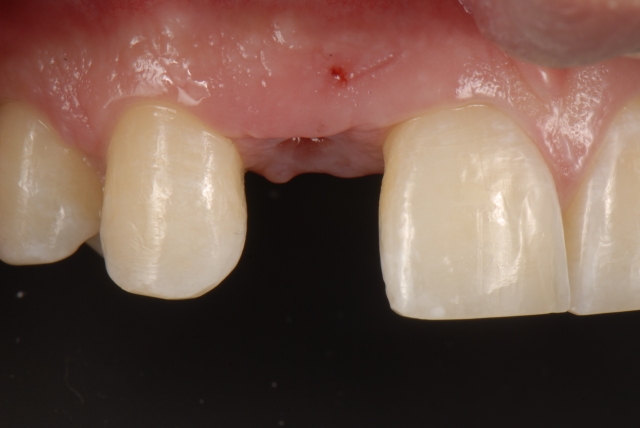

Single-tooth implants in the esthetic zone usually require a provisional restoration. The fabrication of a single-tooth implant-supported restoration requires a careful step-by-step approach to deliver a restoration that will assist the process of soft-tissue sculpting.

Here is a multi-step process showing the fabrication sequence of a screw-retained single-tooth implant provisional restoration of a lateral incisor.